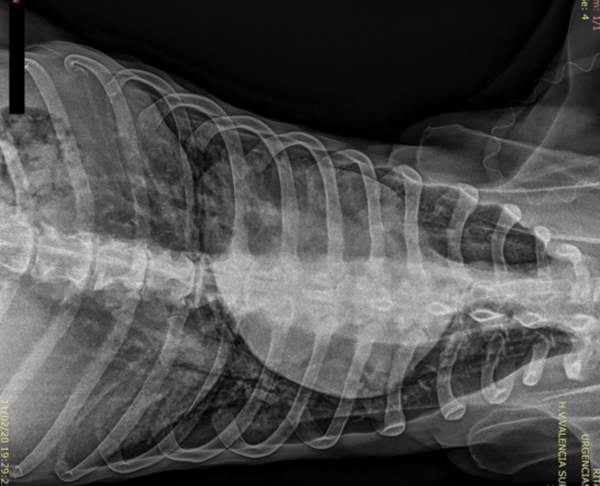

Tras el proceso de estabilizar el distrés respiratorio que presentaba, se realiza estudio radiográfico del tórax

Y se recomienda:

- Revaluar estudio radiográfico tórax.